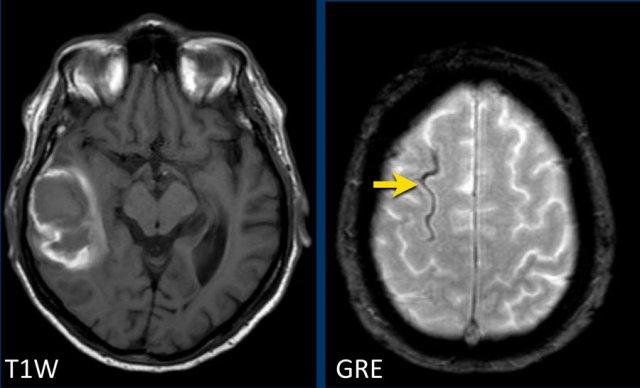

Bệnh nhân CAA này có xuất huyết vi thể, nhiễm sắt bề mặt và nhiều ổ nhồi máu.

Lưu ý ổ xuất huyết ở cầu não (mũi tên vàng).

Có hình ảnh nhiễm sắt bề mặt ở vùng chẩm trái.

Chuỗi xung DWI cho thấy ổ nhồi máu ở thùy chẩm trái và thùy trán phải (kèm theo một số xảo ảnh).